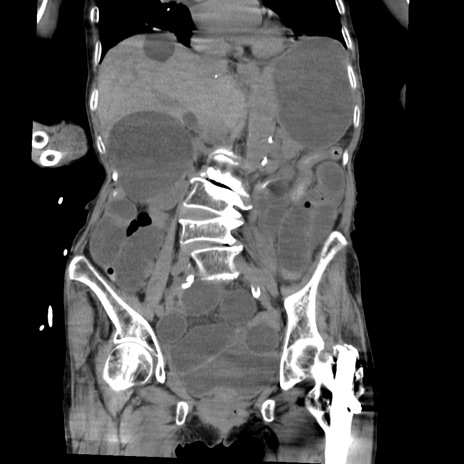

症例27(冠状断像)

【症例】80歳代女性

【主訴】嘔吐、腹痛

【現病歴】数時間前より嘔吐あり。心窩部痛出現し、徐々に右下腹痛あり。その後も数回嘔吐あり救急搬送となる。

【身体所見】腹部は膨隆しているが軟らかく圧痛なし。腸雑音はやや亢進。

【データ】WBC 12000、CRP 19.05